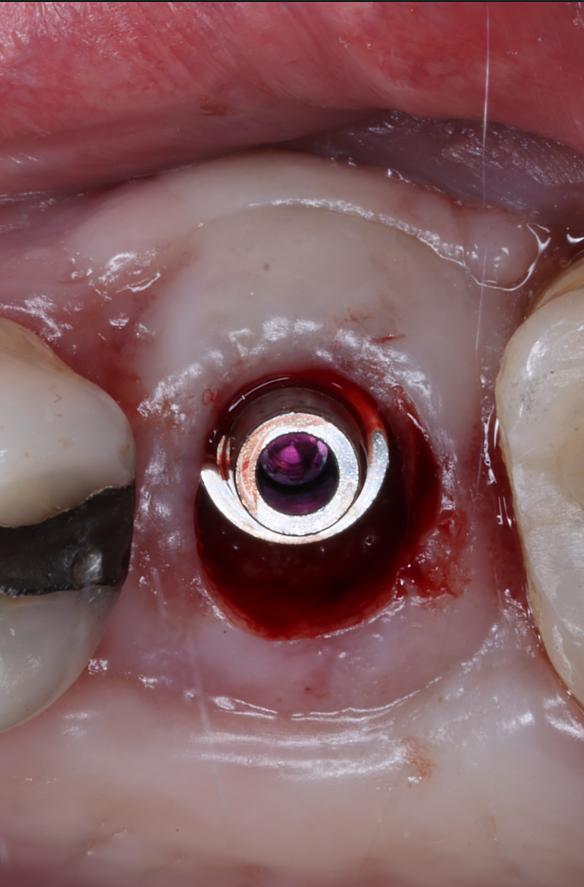

Today, we placed the implant, scanned for the final restoration, just like teaches us to do, and I placed a Neodent healing abutment.

Couple things about this case, I chose to do a tissue punch because the width of the ridge and the amount of attached tissue present. When we use the PTFE membrane for socket preservation, we ultimately grow nice, thick attached tissue, and this is a perfect example of that. I probably only do one or two tissue punches a year.